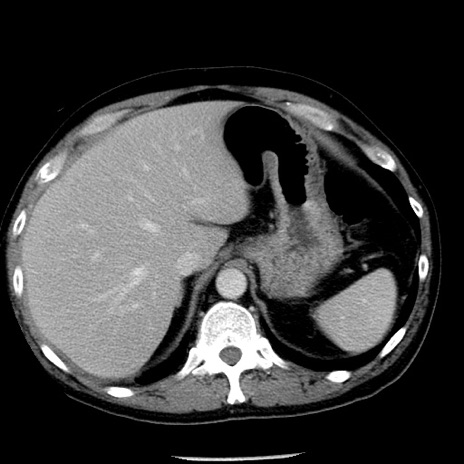

症例29(横断像)

【症例】40歳代男性

【現病歴】2日前から胃痛あり。徐々に周期的な激痛に変化した。本日になっても激痛があるため受診。

【身体所見】意識清明、BT 38-39℃台あり、腹部:膨満、やや硬、右下腹部に圧痛あり。

【データ】WBC 8500、CRP 23.26